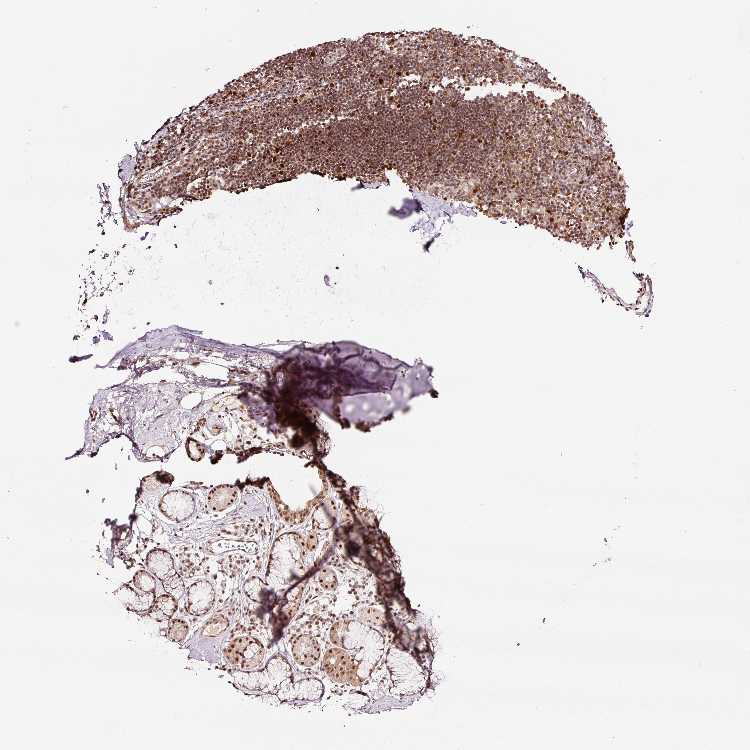

ADIPOSE TISSUE - Antibody stainingi

Antibody staining in the annotated cell types in the current human tissue is reported as not detected, low, medium, or high, based on conventional immunohistochemistry profiling in selected tissues. This score is based on the combination of the staining intensity and fraction of stained cells.

Each image is clickable and will lead to virtual microscopy that enables deeper exploration of all samples and also displays staining intensity scores, fraction scores and subcellular localization as well as patient and tissue information for each sample.

Antibody HPA049123Antibody HPA058507Antibody CAB004557

Adipocytes LowNot detectedMedium